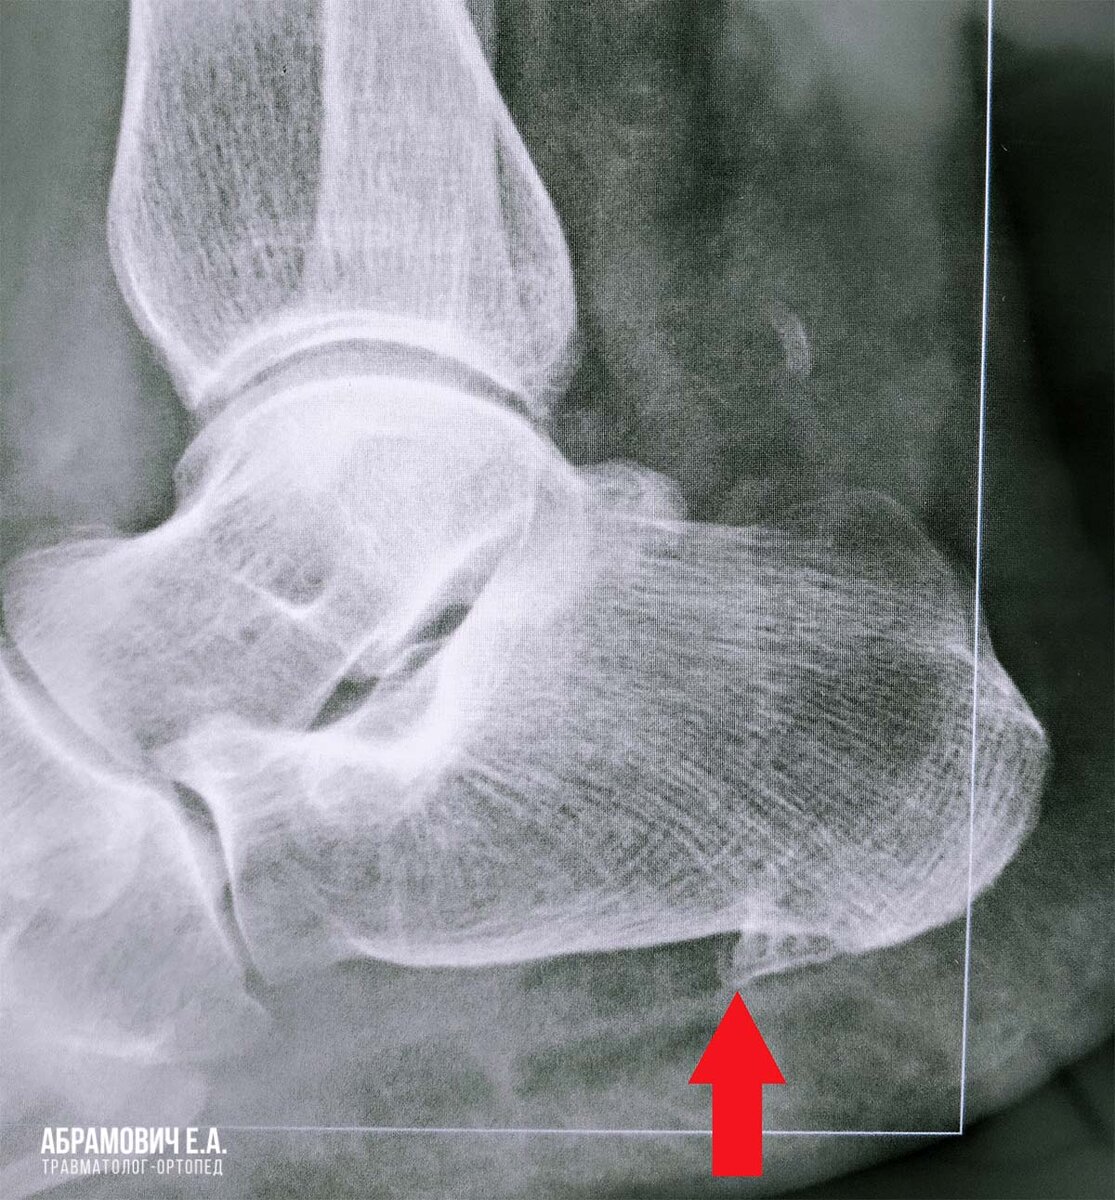

Начать необходимо с обследования. Часто пациента направляют на рентген-снимок, но это даёт лишь общее представление о костных структурах. Вероятней всего пациент получит подтверждение того, что имеется костный нарост и ноль информации о том, есть ли воспаление подошвенной фасции.